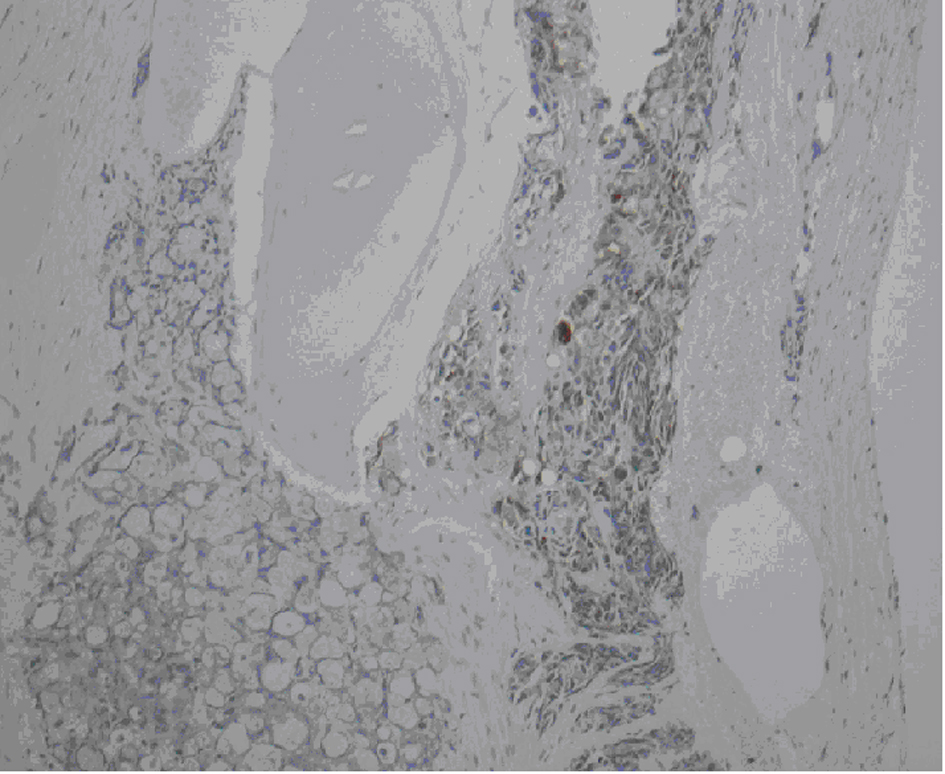

![]() Click for large image | Figure 2. Bone marrow biopsy demonstrating diffuse marrow replacement by metastatic adenocarcinoma. Cellularity to fat ration 100:0. Erythropoiesis and granulopoiesis are decreased. Decreased number of lymphocytes and megakayocytes. Cytokeratin, PSA, and CEA stains are positive. |

Because of persistent dyspnea, a CT of the chest was ordered which was negative for pulmonary embolism in addition ground-glass opacities, nodules, and mediastinal lymphadenopathy. Endobrochial ultrasound (EBUS) and Bronchoalveolar lavage (BAL) were performed which were positive for malignancy, consistent with adenocarcinoma. Bone marrow biopsy was obtained to further assess the etiology of his pancytopenia, which showed diffuse bone marrow replacement by metastatic adenocarcinoma (Fig. 1). Cytokeratin, PSA, and CEA stains were all positive. CEA and PSA were elevated at 165 ng/mL and 132 ng/mL respectively. Patient stated last PSA was done 7 years ago was normal.

Once adenocarcinoma has been identified, immunohistochemical markers may be utilized to help determine the lineage of the tumor. This patient presented with pancytopenia, so a bone marrow biopsy was obtained. Similar to findings in the lung, this biopsy demonstrated adenocarcinoma. Cytokeartin, PSA, CEA, and P63 were all positive. It is important to understand the pattern of these markers and to correlate them with the clinical scenario in order to truly maximize their efficacy.